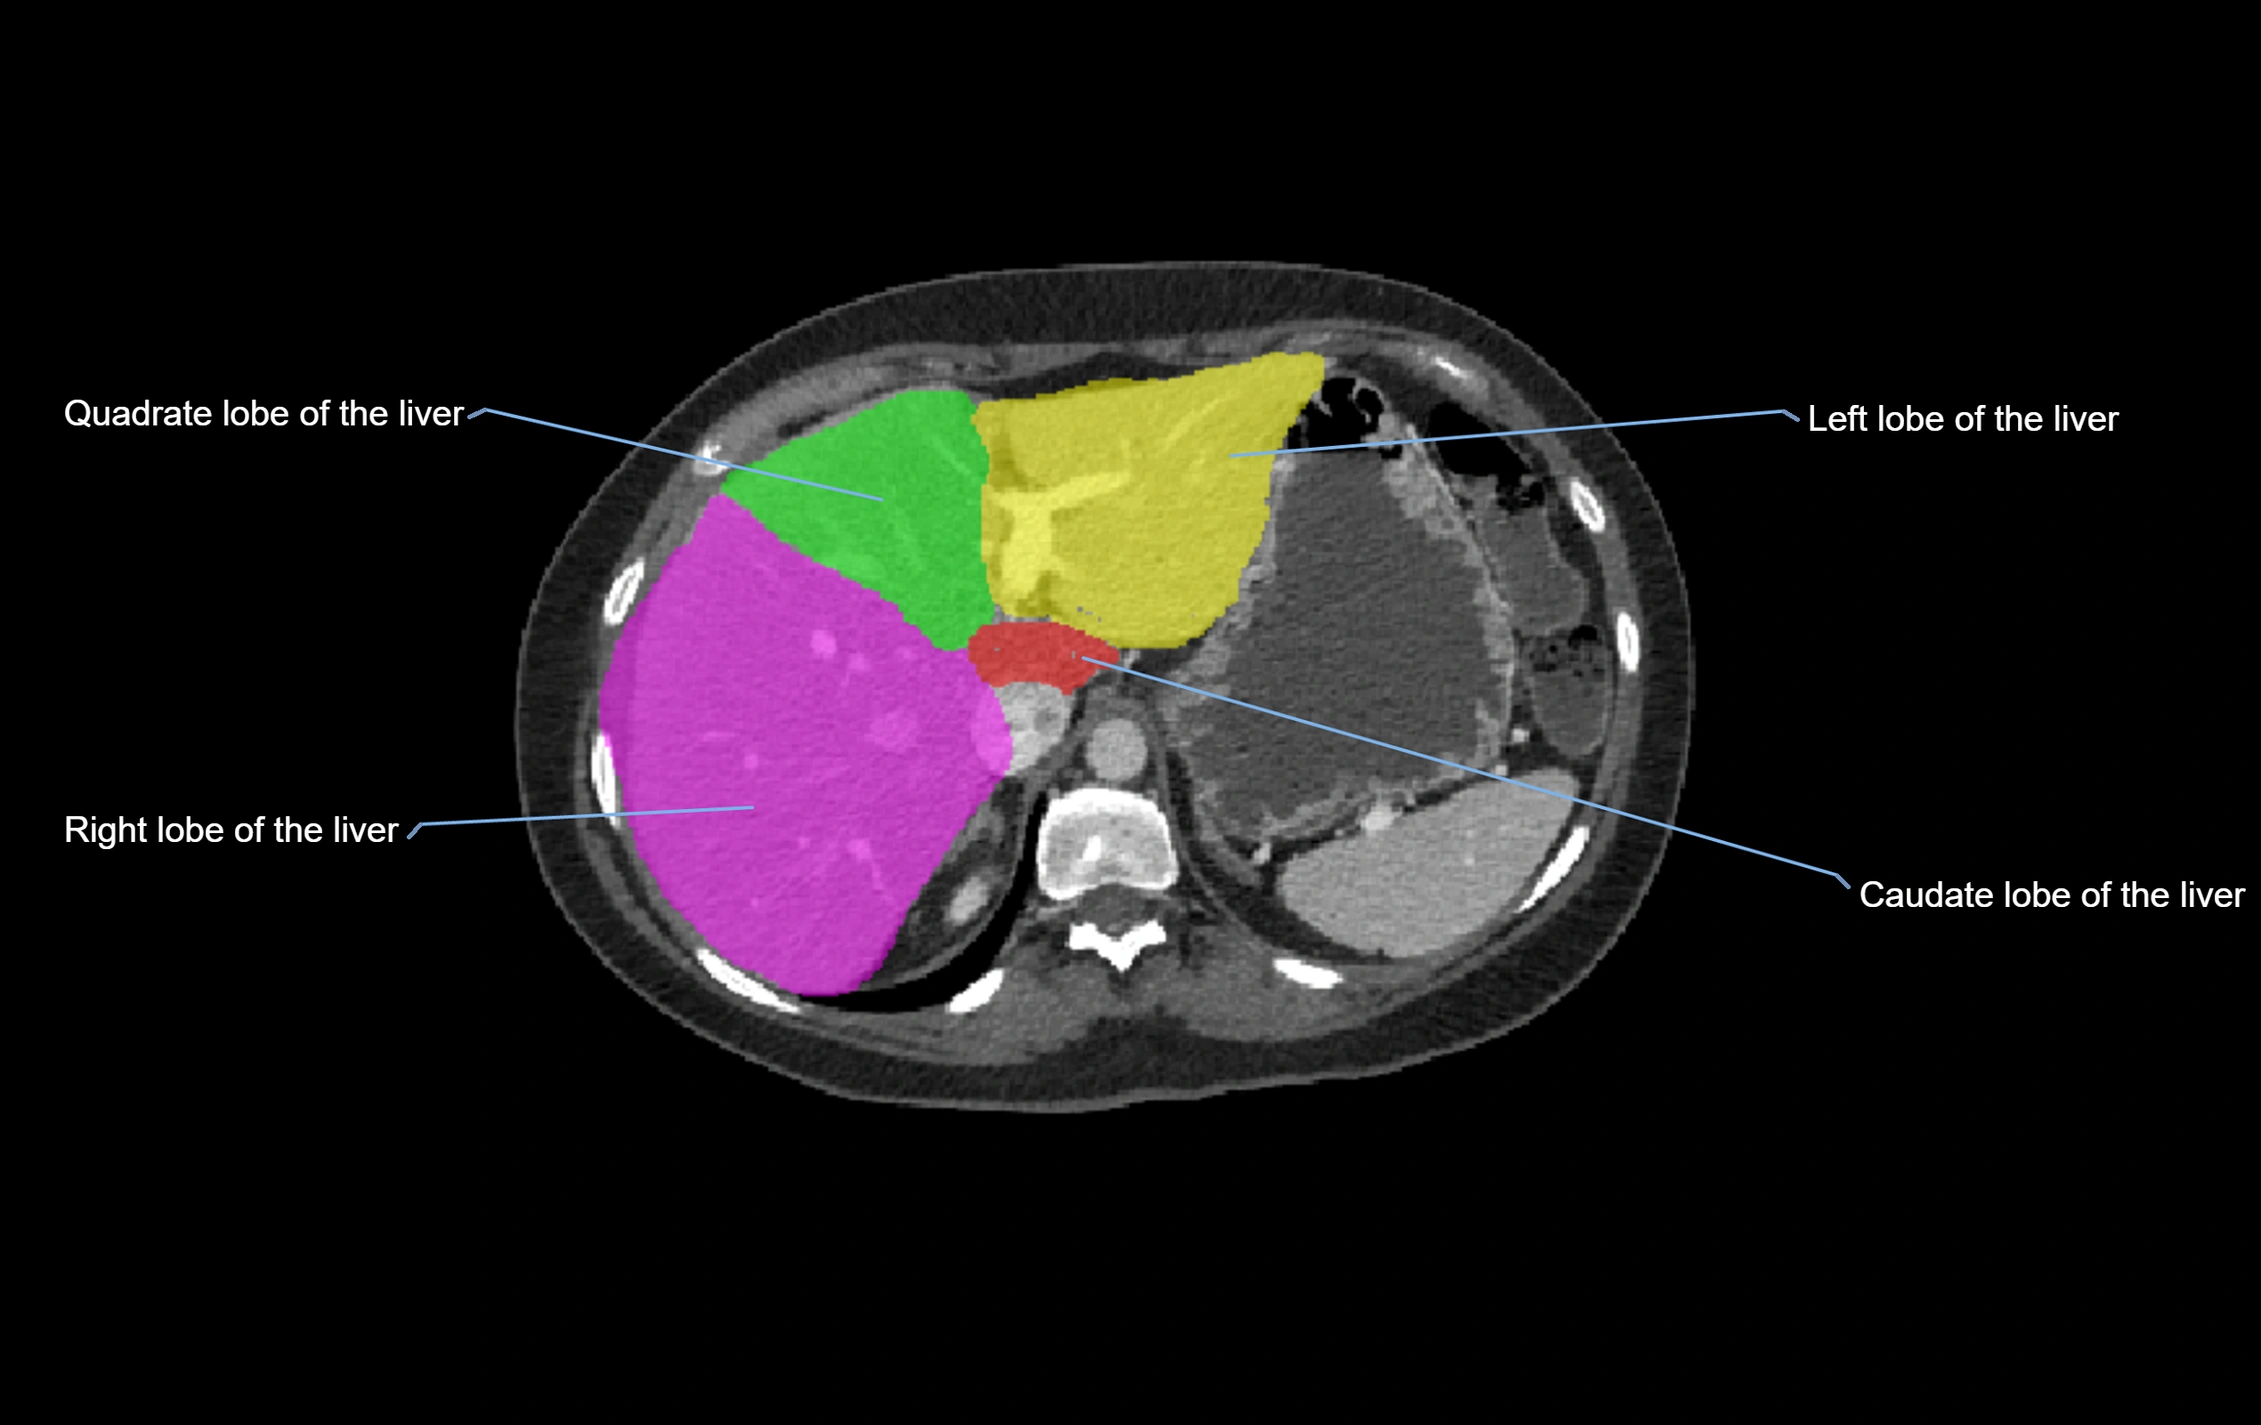

The caudate lobe of the liver is a distinct anatomical subdivision of the liver, designated as segment I in Couinaud’s classification. It lies on the posterior surface of the liver, between the fissure for the ligamentum venosum (left boundary) and the groove for the inferior vena cava (IVC) (right boundary). Superiorly, it is related to the posterior liver surface, and inferiorly it is separated from the left lobe by the porta hepatis.

CT Image

image